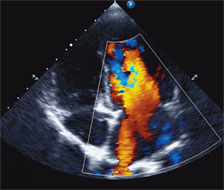

An echocardiogram showed evidence of severe right ventricular hypertension due to elevated pulmonary pressure, which was confirmed via catheterization. We diagnosed her with IPAH and immediately started her on pulmonary vasodilators in an effort to reduce the pulmonary pressures.

Correcting the lesion would require several interventional radiology procedures to occlude the AVM. However, tolerating these procedures was going to be difficult in the setting of severe PH. Therefore, after confirming his PH by echocardiography and cardiac catheterization, he was quickly escalated on PH-specific medications. This included a continuous subcutaneous infusion of a prostacyclin (treprostinil) to reduce the PH and improve cardiovascular function. It is routinely used in adults with severe pulmonary hypertension, but at this time treprostinil was rarely used in young infants.4 However, given our familiarity with this drug and our experience with infant PH, we felt comfortable using it for HT, who tolerated it very well.